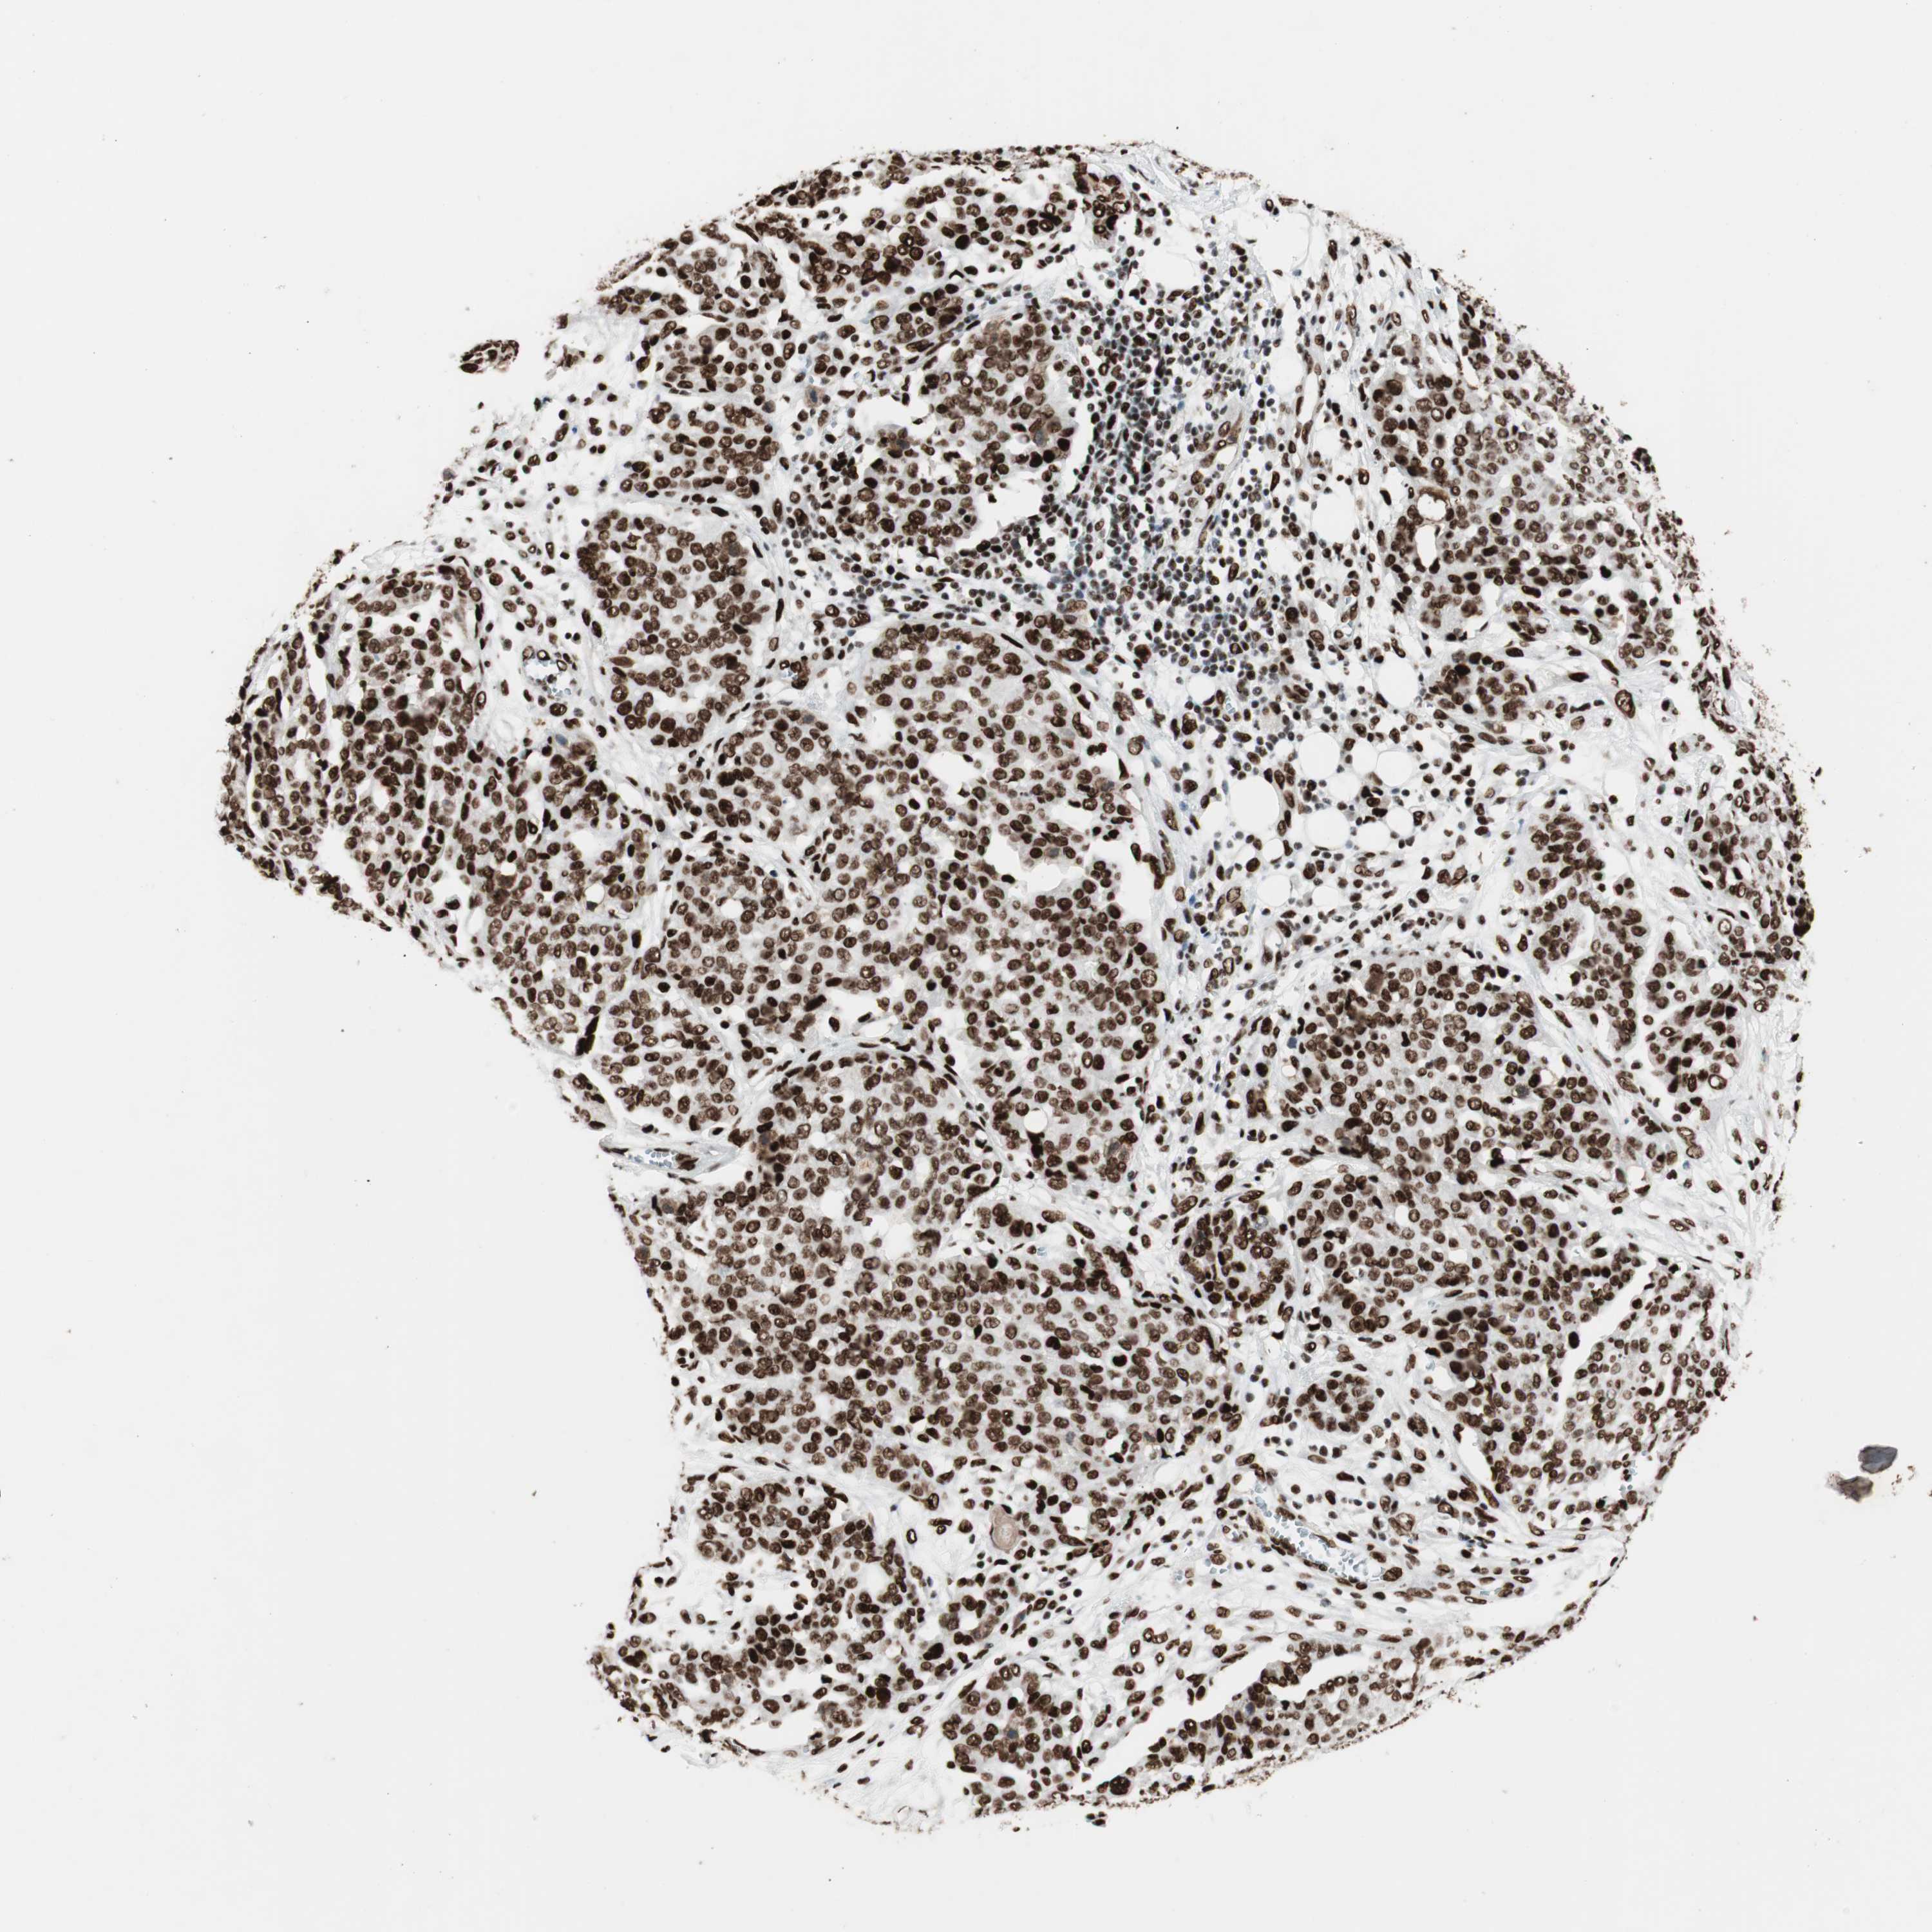

OVARIAN CANCER - Protein expressioni

A mouse-over function shows sample information and annotation data. Click on an image to view it in a full screen mode. Samples can be filtered based on level of antibody staining by selecting one or several of the following categories: high, medium, low and not detected. The assay and annotation is described here.

Note that samples used for immunohistochemistry by the Human Protein Atlas do not correspond to samples in the TCGA dataset.

Antibody stainingi

Antibody staining in the annotated cell types in the current human tissue is reported as not detected, low, medium, or high, based on conventional immunohistochemistry profiling in selected tissues. This score is based on the combination of the staining intensity and fraction of stained cells.

Each image is clickable and will lead to virtual microscopy that enables deeper exploration of all samples and also displays staining intensity scores, fraction scores and subcellular localization as well as patient and tissue information for each sample.

Antibody HPA012510

Antibody CAB008388

Staining

High

Medium

Low

Not detected

Intensity

Strong

Moderate

Weak

Negative

Quantity

>75%

75%-25%

<25%

None

Location

Nuclear

Cytoplasmic/membranous

Cytoplasmic/membranous,nuclear

Cystadenocarcinoma, serous, NOS